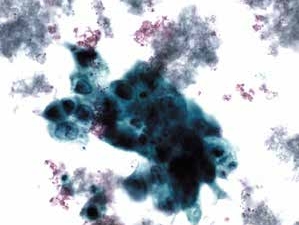

图4-69 非角化型鳞癌(高倍、液基、巴氏染色)

癌细胞成团排列,圆形、梭形,胞核深染,染色质粗颗粒状,核质比高,肿瘤素质可见。